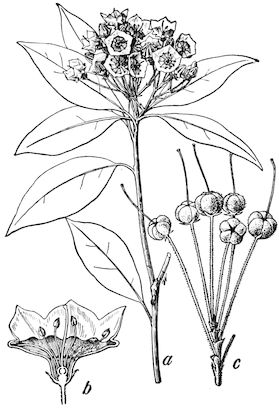

Fig. 3.—Pig suffering from osseous cachexia (fourth stage).

114. The fourth phase, or period of osteomalacia, i.e. softening of the bones, is also the last. It is rarely seen in large animals like horses and oxen, because accidents so often accompany the preceding stages and necessitate slaughter; but it is common in goats and pigs.

The flat bones are particularly liable to this change, which is common to domesticated animals. The bones of the head are the first to suffer; later those of the pelvis. The lower jaw becomes swollen, particularly about the centre of the branches which may attain three, four, or five times, their normal thickness.

The depression in the submaxillary space disappears. The upper jaw undergoes similar changes, becoming deformed and thickened until the cavities of the sinuses and the hollow appearance of the palate are lost, while the face is so changed that it cannot be recognised as that of a horse, goat, etc.

The molar teeth are almost buried, their tables alone being visible at the bottom of a depression, the edges of which rise above the neighbouring parts (pig).

Mastication is clearly impossible, the jaws appear paralysed, the muscles powerless, and only swallowing is possible, a fact which explains why life is only prolonged to this stage in animals which can be fed with a spoon or bottle (pigs and goats). The bones of the cranium, although greatly changed in texture, are always less deformed than those of the face.

In the goat, the disease shows some slight peculiarities. Thus, in the second phase, during which goats and sheep suffer so markedly from lameness and pain in the bones, goats often walk on the knees. The disease, however, is uncommon in these animals. The phase of osteoclastia is also less marked and fractures are rare, because the animals weigh less and also because they are less exposed to falls and violent shocks. The bones, nevertheless, are extremely fragile and fractures may be produced at will.

Osteomalacia, on the other hand, is always well marked.

Regarding the development of the disease in pigs, we may repeat what has just been said respecting the goat. Walking on the knees is often one of the first signs, fractures are somewhat rare, and the period of softening and deformity is always very noticeable.